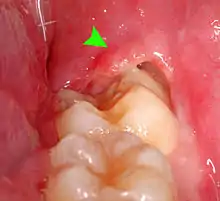

| Pericoronitis associated with the lower right third molar (wisdom tooth). | |

Pericoronitis is inflammation of the soft tissues surrounding the crown of a partially erupted tooth,[1] including the gingiva (gums) and the dental follicle.[2] The soft tissue covering a partially erupted tooth is known as an operculum, an area which can be difficult to access with normal oral hygiene methods. The hyponym operculitis technically refers to inflammation of the operculum alone.

Pericoronitis is caused by an accumulation of bacteria and debris beneath the operculum, or by mechanical trauma (e.g. biting the operculum with the opposing tooth).[3] Pericoronitis is often associated with partially erupted and impacted mandibular third molars (lower wisdom teeth),[4] often occurring at the age of wisdom tooth eruption (15-26).[5][6] Other common causes of similar pain from the third molar region are food impaction causing periodontal pain, pulpitis from dental caries (tooth decay), and acute myofascial pain in temporomandibular joint disorder.

- Tenderness, erythema (redness) and edema (swelling) of the tissues around the involved tooth,[9] which is usually partially erupted into the mouth. The operculum is characteristically very painful when pressure is applied.[2]

- Formation of pus,[9] which can be seen exuding from beneath the operculum (i.e. a pericoronal abscess), especially when pressure is applied to the operculum.[2]

- Signs of trauma on the operculum, such as indentations of the cusps of the upper teeth,[9] or ulceration.[4] Rarely, the soft tissue around the crown of the involved tooth may show a similar appearance to necrotizing ulcerative gingivitis.[11]